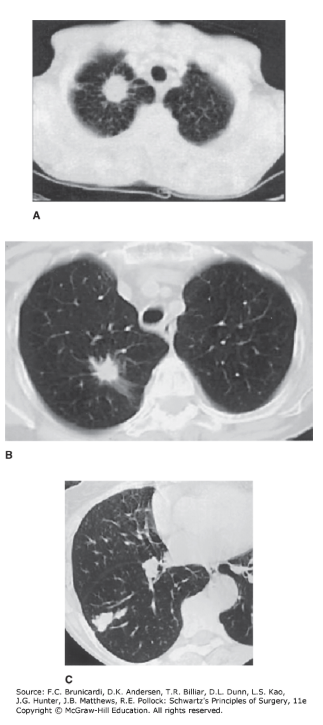

Solitary And Multiple Pulmonary Nodules Radiology Key